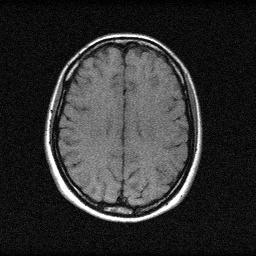

About the Imaging Modality

MRI forms images by exciting hydrogen nuclei with RF pulses in a strong magnetic field (1.5-7T) and measuring the emitted RF signal with receive coils. Spatial encoding uses gradient fields to map signal frequency and phase to spatial position, acquiring data in k-space (spatial frequency domain). The forward model for parallel imaging is y_c = F_u * S_c * x + n_c where F_u is the undersampled Fourier transform, S_c are coil sensitivity maps, and n_c is complex Gaussian noise. Accelerated MRI undersamples k-space (4-8x) and uses SENSE, GRAPPA, or deep-learning (E2E-VarNet) for reconstruction.

Magnetic Resonance Imaging measures the precession of hydrogen nuclear spins in a strong magnetic field (1.5-7 T). Radiofrequency pulses tip spins away from equilibrium, and gradient fields spatially encode the MR signal into k-space (spatial frequency domain). The image is obtained by inverse Fourier transform of k-space data. Contrast depends on tissue T1, T2, and proton density via the pulse sequence timing parameters.